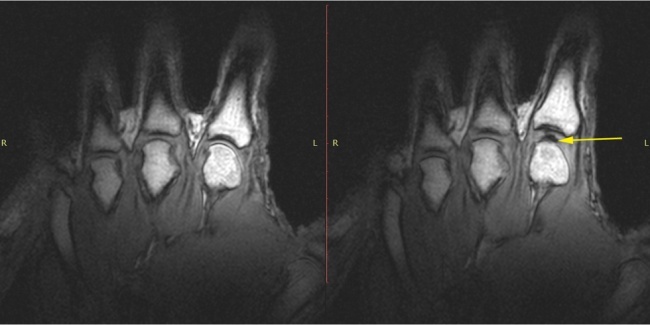

Хруст в суставах - это звук трескающегося характера возникающий при пассивных или активных движениях . Мастерок .жж .рф . Хочу все знать . Вредно ли хрустеть суставами?